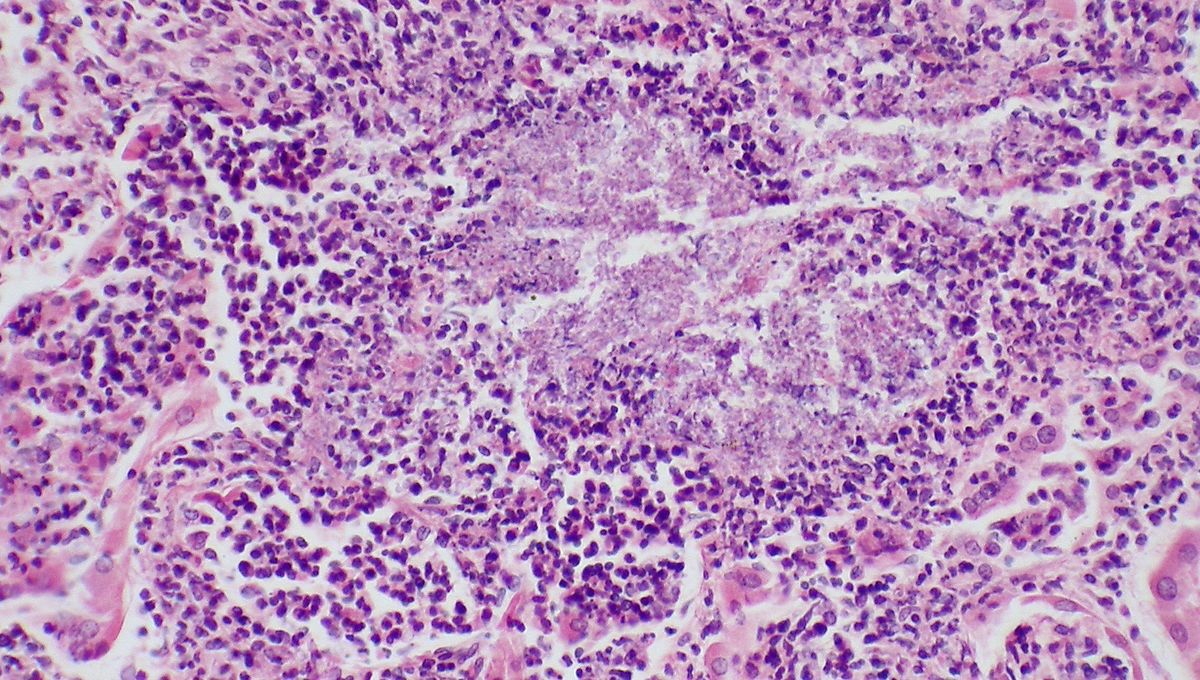

New Type Of Lethal Fungus That Is “Serious Threat” To Public Health Discovered

Candida auris is an often drug-resistant and sometimes deadly fungal pathogen.